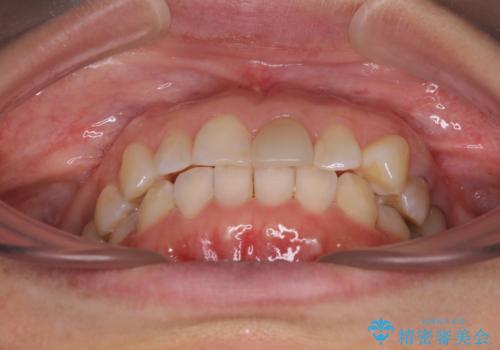

当院では治療前の歯列が整っていない限り、下顎前歯の舌側をワイヤーで固定するようにしています。下顎のみの部分矯正としたことで、マウスピース保定の負担を軽減することができました。

上顎は、失活して歯の色が変色しているため、将来的に補綴治療で自然な口元に仕上げていきたいとのことでした。